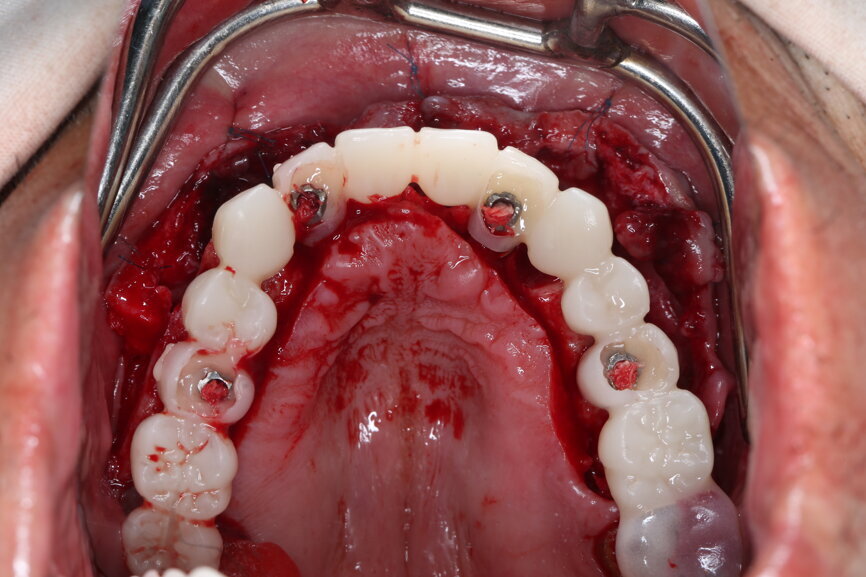

On the day of surgery, we prepared for the surgical protocol provided by the implant planning software, which guided us on the drilling sequence and the use of the appropriate instruments for the implant bed preparation (Figs. 30a & b). After the fixation pins had been allocated, teeth #17, 16, 15, 13, 12, 22, 23 and 24 were atraumatically extracted and alveolectomy was performed using a bone reduction guide (Figs. 31–36). Four implants (Straumann BLX; regular base; diameter: 4.5 mm; length: 12.0 mm) were placed, two straight implants in the anterior and two titled implants in the posterior. All the implants were stabilised to a torque of 50 Ncm (Figs. 37–43), and the SRAs were placed on top. The SRAs on the posterior implants had an angulation of 30° (diameter: 4.6 mm; gingival height: 3.5 mm) and on the anterior implants an angulation of 17° (diameter: 4.6 mm; gingival height: 3.5 mm; Figs. 44 & 45).

The bite registration guide was fixed with pins, and the open-tray impression copings were placed on the SRAs of the anterior implants, which were fixed with the guide using flowable composite and then sent to the laboratory (Figs. 46–50). Afterwards, we checked the CAD/CAM temporary restoration which had been designed and milled before surgery (Fig. 51), and protective caps were placed on the SRAs, followed by bone grafting using cerabone granules (botiss biomaterials) with a 1–2 mm grain size in the extraction sockets and suturing (Figs. 52–54).